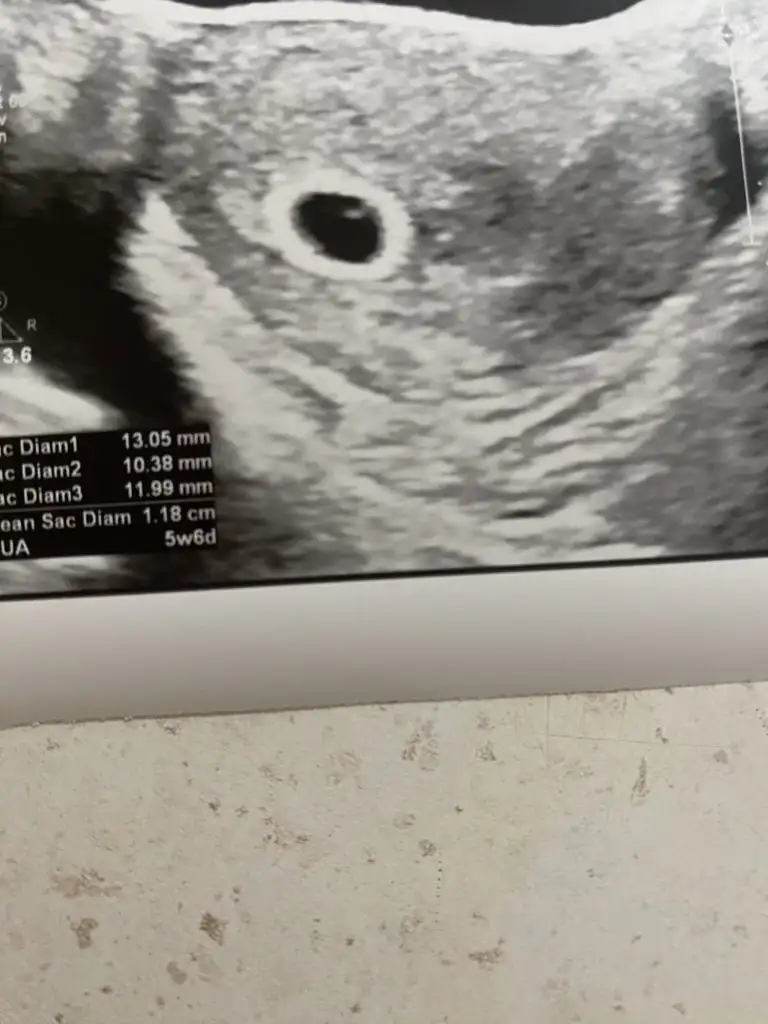

Şimdi geldim eve canım bu doktor bakar bakmaz gördü hatta çok şaşırdı dün görünmemesine. Dünkü doktorun cihazı eski değil bozukmus bence bidaha gitmeyin falan dedi rahatladım baya♥️ çok şükür hiçbir sıkıntı yok 😘 şu kesenin içindeki beyaz nokta bebek mi yolk kesesi mi onu bilemedim

Eklentiler

• IMG_8658.webp

IMG_8658.webp

27,8 KB · Görüntüleme: 66